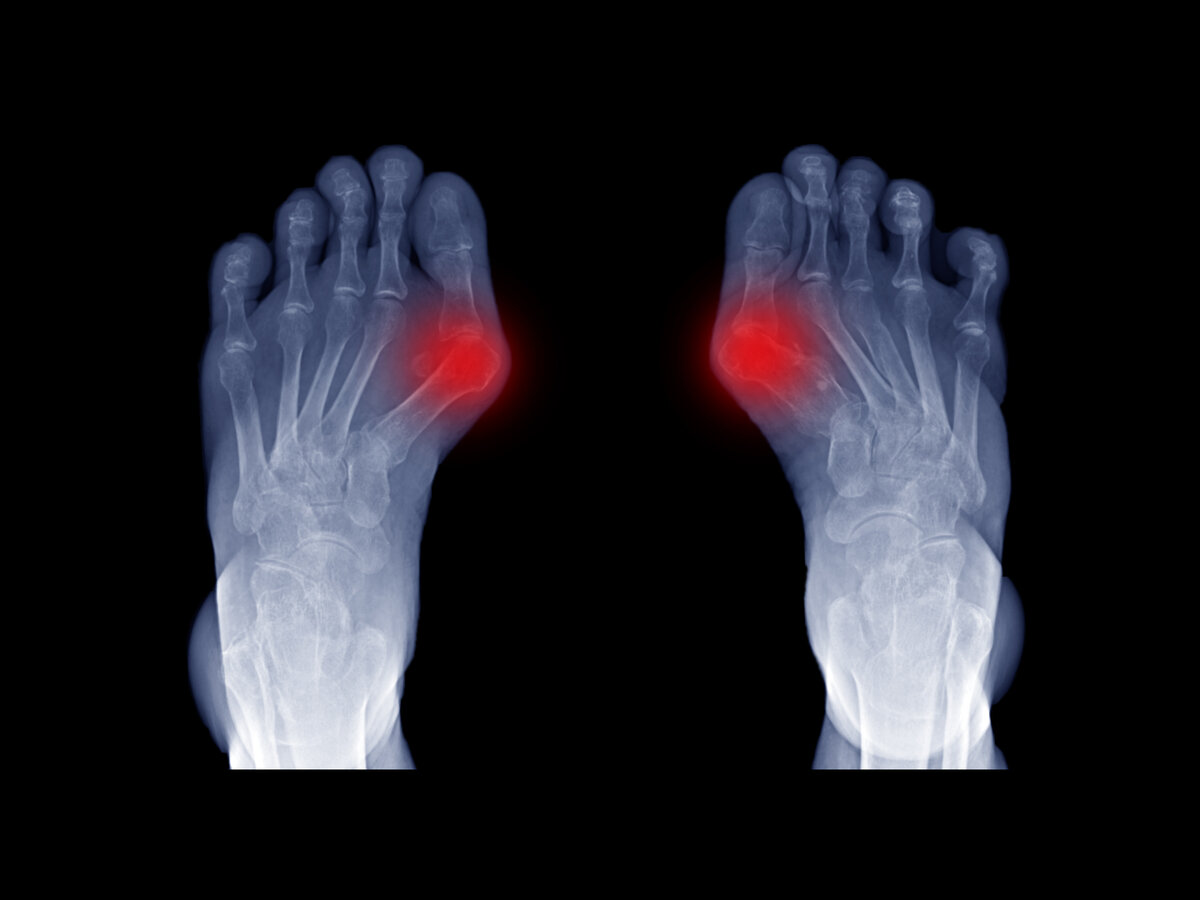

То, что в обиходе мы называем косточкой на большом пальце ноги, на научном языке звучит как вальгусная деформация пальца стопы. Никакой «шишки» или дополнительной отдельной косточки на ноге нет. Это только так кажется. На самом деле — это отклонение первой плюсневой кости стопы во внутреннюю сторону с одновременным наклонением большого пальца наружу.

Если же стопа уже расплющена, стала шире, а мы все по-прежнему ходим в тесной узкой обуви, то происходит следующее. Первая плюсневая кость постепенно отклоняется от своего правильного положения. Смещение пальца и этой кости ведет к образованию так называемого вальгусного угла. Головка плюсневой кости является его вершиной, которая со временем утолщается и преобразуется в ту самую косточку на большом пальце н6оги, которую не скроешь.

Очень часто при вальгусной деформации пальца стопы косточки появляются не только на больших пальцах ног, но и возле мизинца.